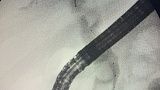

Отмечатся юкстапапиллярное расположение большого дуоденального сосочка тип-3. Канюляция папиллотомом pull-type ,контрастирование водорастворимым контрастом .

Рентгенологическая картина расширенния желчных протоков и наличие конкрментов в холедохе. Произведена эндоскопическая ограниченная папиллосфинктеротомия, отмечалось поступление темной желчи. Ревизия корзиной Дормия дали основания полагать ,что конкременты плотной консистенции.

Учитывая состояние пациента, большой степени вероятности осложнений и наличие крупных конкрементов в холедохе , принято решение следовать общепринятой тактике лечения при юкстапапиллярном расположении БДС - воздержаться от одноэтапного проведения операции с литэкстракцией. Произведено стентирование холедоха пластиковым стентом типа Pig-tail 10 Fr-130 мм, чем достигнуто адекватное дренирование желчных путей. Послеоперационный период протекал без осложнений. Биохимический анализ крови: билирубин общий-17.0 , билирубин прямой -13.0 , билирубин непрямой - 4, с-реактивный белок -24.3, скорость клубочковой фильтрации-37,4. По представленным результатам обследования в послеоперационом периоде, можно отметить положительную динамику в показателях пигментного обмена. Пациент в удовлетворительном состоянии выписан на амбулаторное лечение .